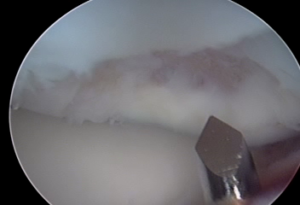

A pin is used to make perforations in bone.

Perforations in the bone allow marrow elements to gain access to the defect and stimulate healing.